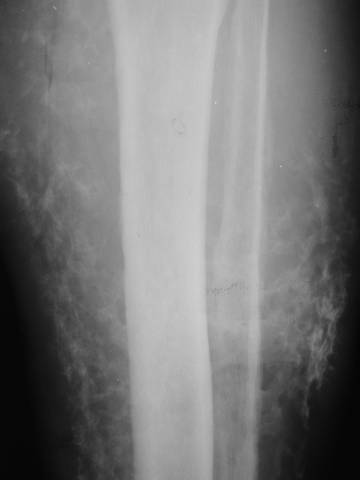

Chronic Venous Insufficiency